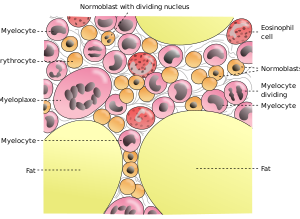

النخاع

العظام الطويلة تكون متصلة بالعضلات الهيكلية بالأوتار. ترتيط العظام بعضها ببعض بواسطة المفاصل والتي ترتبط بلأربطة. يوجد نخاع العظم الاحمر في المادة الخلوية للعظم الاسفنجي، مما يسمح للعظم من انتاج خلايا الدم الحمراء. وأيضاً يوجد نخاع العظم في ساق العظام، ويقوم بتوليد خلايا الدم البيضاء.

التخليقية